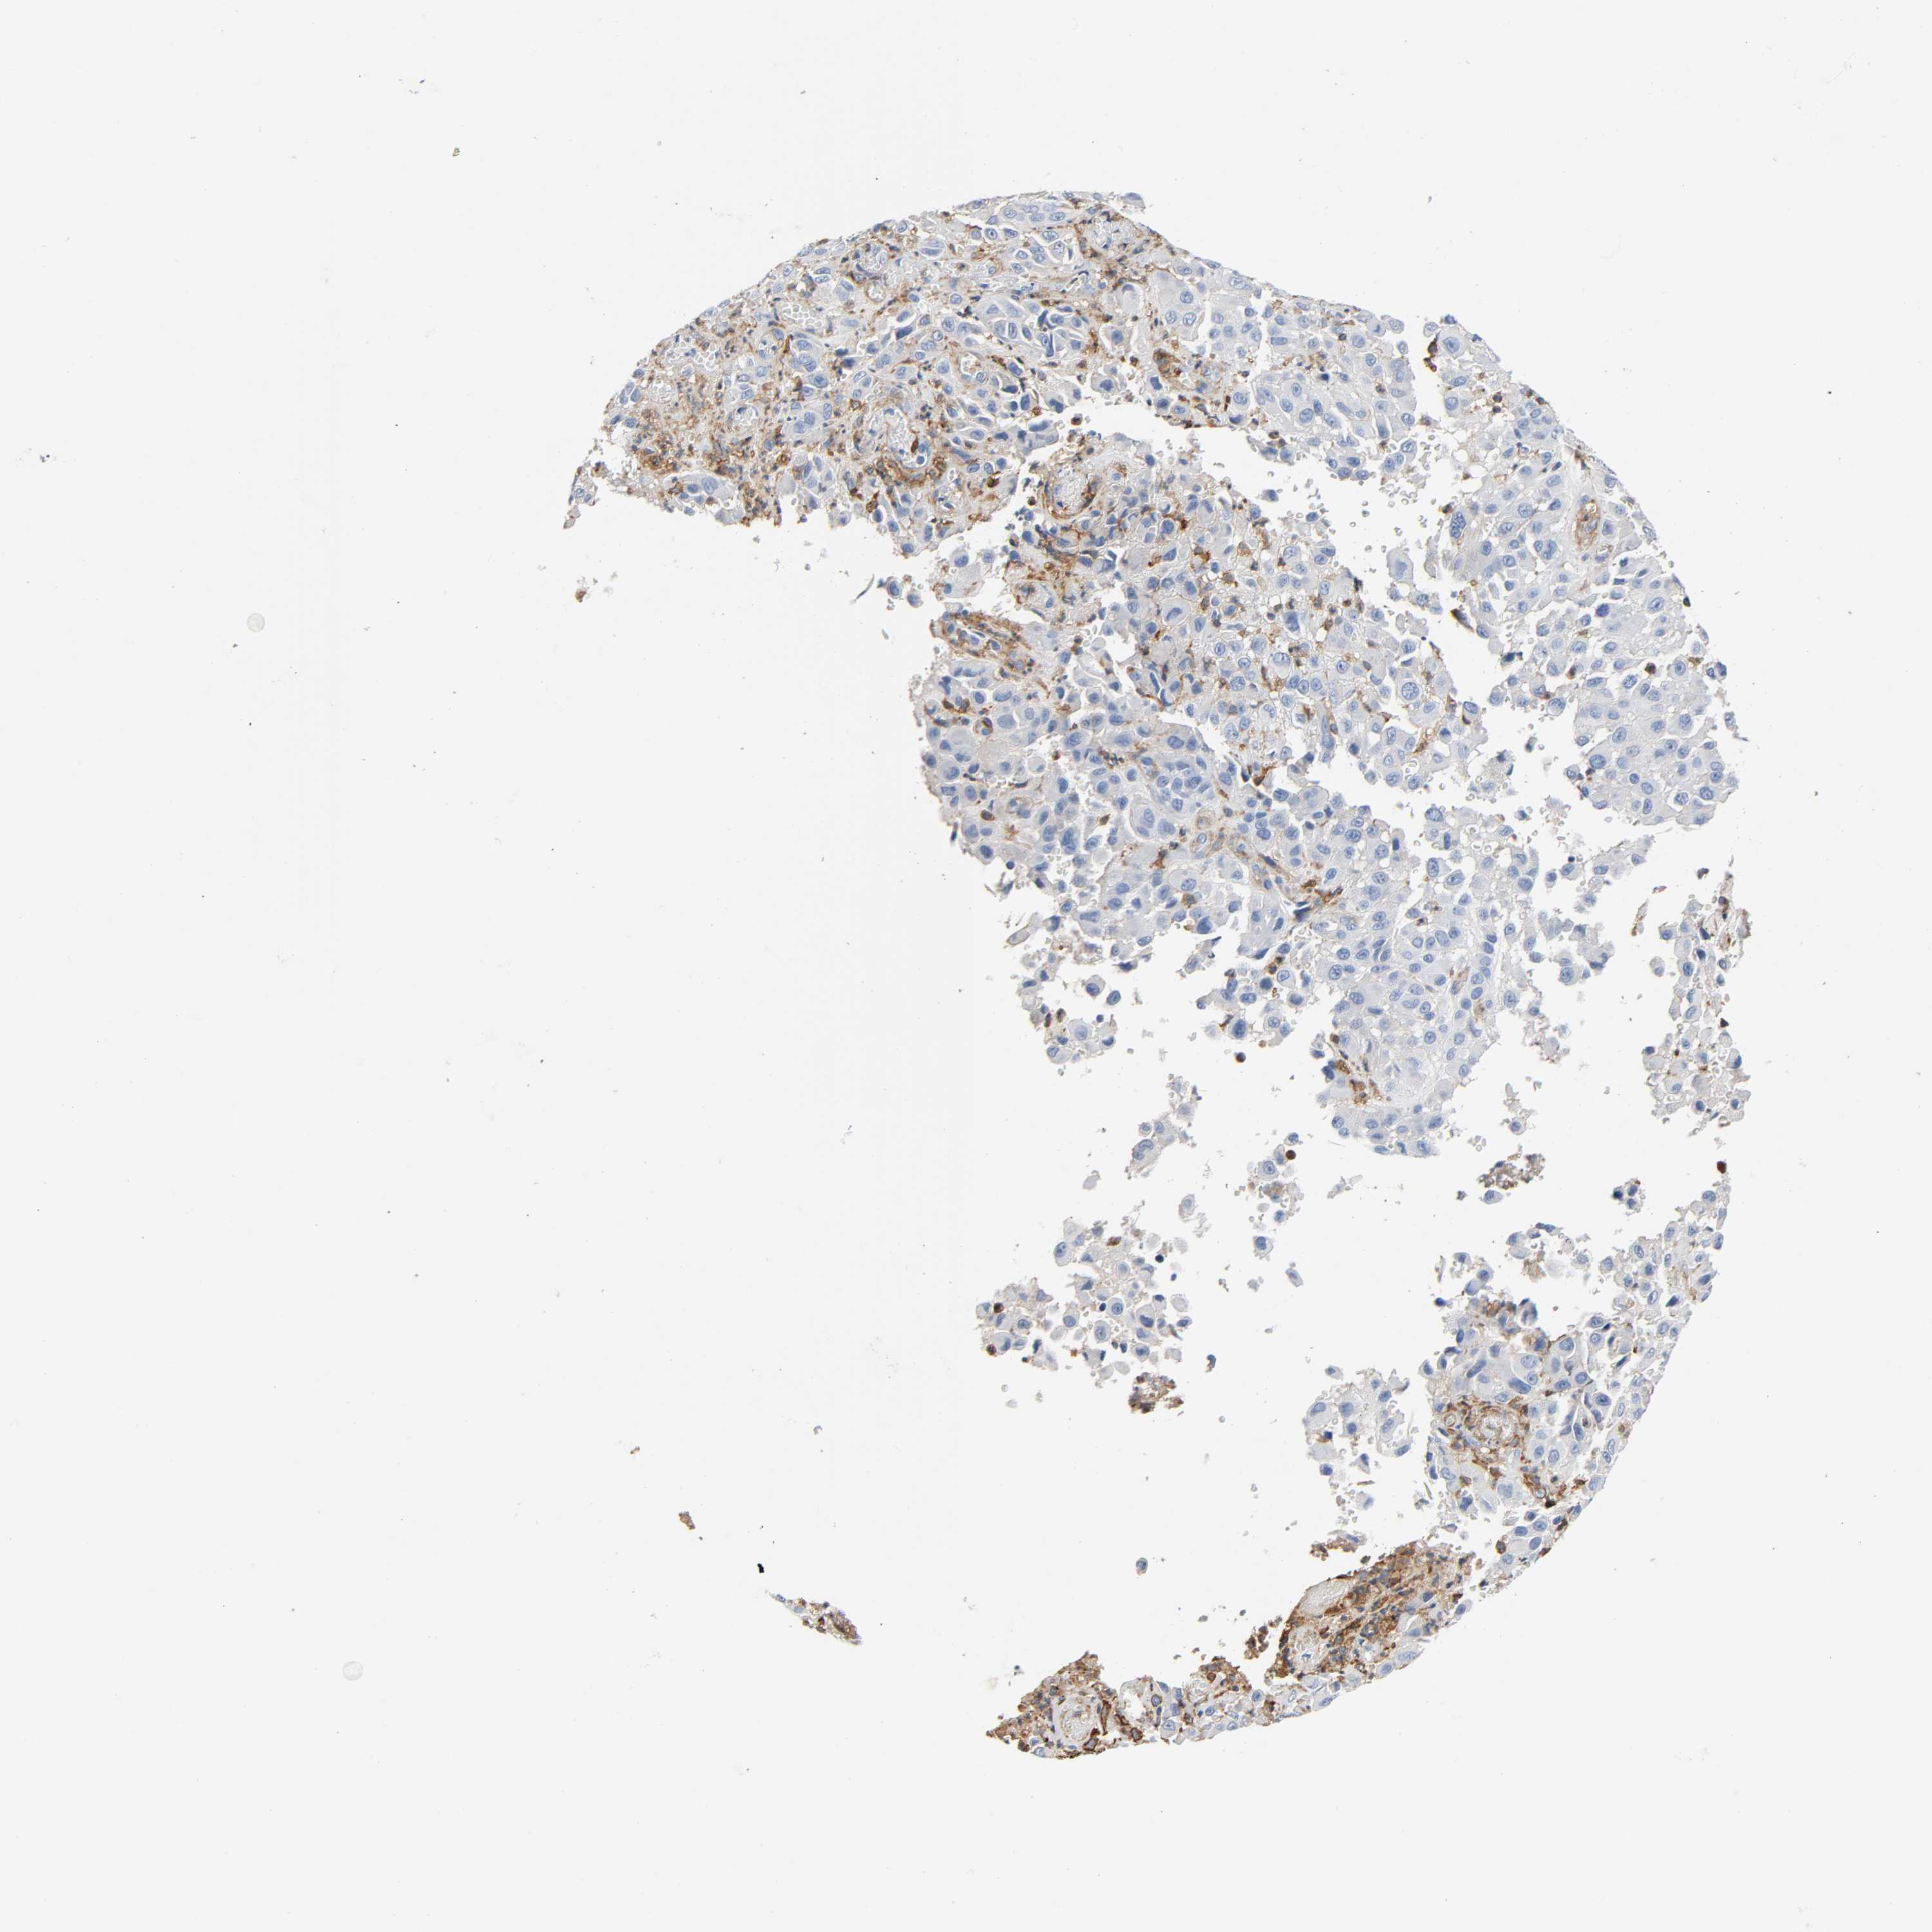

MELANOMA - Protein expressioni

A mouse-over function shows sample information and annotation data. Click on an image to view it in a full screen mode. Samples can be filtered based on level of antibody staining by selecting one or several of the following categories: high, medium, low and not detected. The assay and annotation is described here.

Note that samples used for immunohistochemistry by the Human Protein Atlas do not correspond to samples in the TCGA dataset.

Antibody stainingi

Antibody staining in the annotated cell types in the current human tissue is reported as not detected, low, medium, or high, based on conventional immunohistochemistry profiling in selected tissues. This score is based on the combination of the staining intensity and fraction of stained cells.

Each image is clickable and will lead to virtual microscopy that enables deeper exploration of all samples and also displays staining intensity scores, fraction scores and subcellular localization as well as patient and tissue information for each sample.

Antibody HPA004625

Staining

High

Medium

Low

Not detected

Intensity

Strong

Moderate

Weak

Negative

Quantity

>75%

75%-25%

<25%

None

Location

Nuclear

Cytoplasmic/membranous

Cytoplasmic/membranous,nuclear

Malignant melanoma, NOS